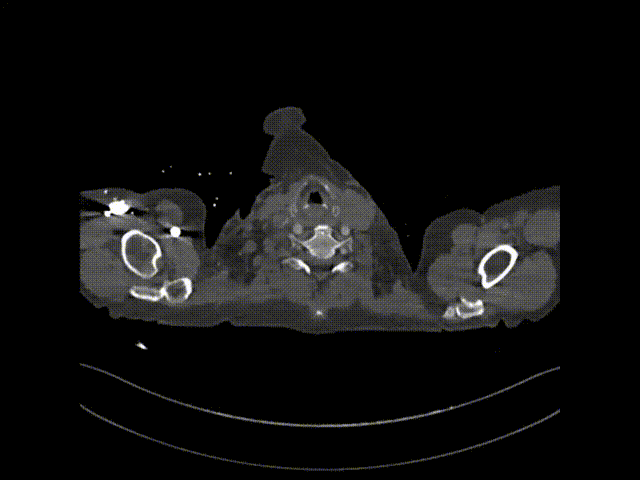

术后随访

患者出院前进行CTA复查,可见溃疡隔绝完全,弓上分支血管及冠状动脉通畅。

术后CTA

术后3D动态

术后3D动态 grey

术后3D重建